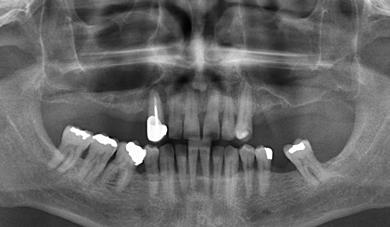

Estudios radiográficos de inicio

En la radiografía lateral de cráneo (Figura 4) se ve la aparatología con la que llegó la paciente, el perfil es convexo, hiperdivergente y las vías aéreas permeables.

En la radiografía panorámica (Figura 5) se observan en 20 dientes los brakets viejos, en los molares 16, 27 las bandas, el canino 13 retenido en el paladar, el botón de Nance, la

ausencia de molares 26, 46. Elmolar 16 tiene un tratamiento endodóntico

Figura 5. Radiografía panorámica de inicio. Figura 6. Progreso cierre de frente, derecha e izquierda. Figura 7. Frente sonrisa, perfil inicio y final.

En las radiografías panorámicas (Figura 11), en la comparación inicio el botón de Nance, en la final se ve sin el canino retenido, el paralelismo radicular, con la ligera perdida ósea con la que llegó la paciente en la zona antero inferior y cuadrante 4, al final continúa sin cambios.

Figura 11. Comparativa Rx Panorámica inicio final.